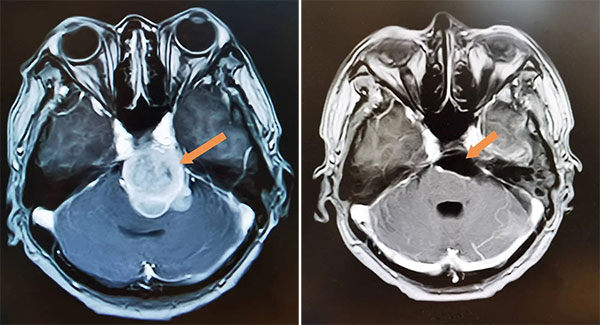

三年前,她感到头疼一天比一天加重,视物双影的现象再次出现,复查的结果令人心惊:经过10多年的缓慢生长,肿瘤体积已经十分巨大,占据中颅凹,岩骨天幕裂孔区,中上斜坡。脑干、双侧大脑脚、丘脑下部等重要神经结构受压并出现脑积水。手术已成唯一选择。

图为:手术前(左图)和手术后(右图),肿瘤全切除,脑干受压解除。